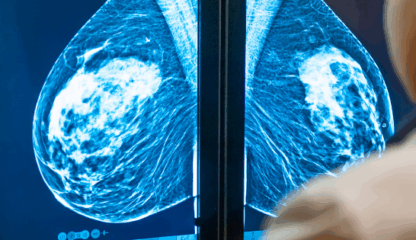

When Deirdre Hall had her routine mammogram last summer, everything seemed perfectly normal. Her radiologist saw no signs of cancer — no shadows, lumps, or irregular patches. But then, artificial intelligence intervened. The screening software had circled a small area in the upper part of Hall’s left breast that it found suspicious. Because of that […]

- mammogram